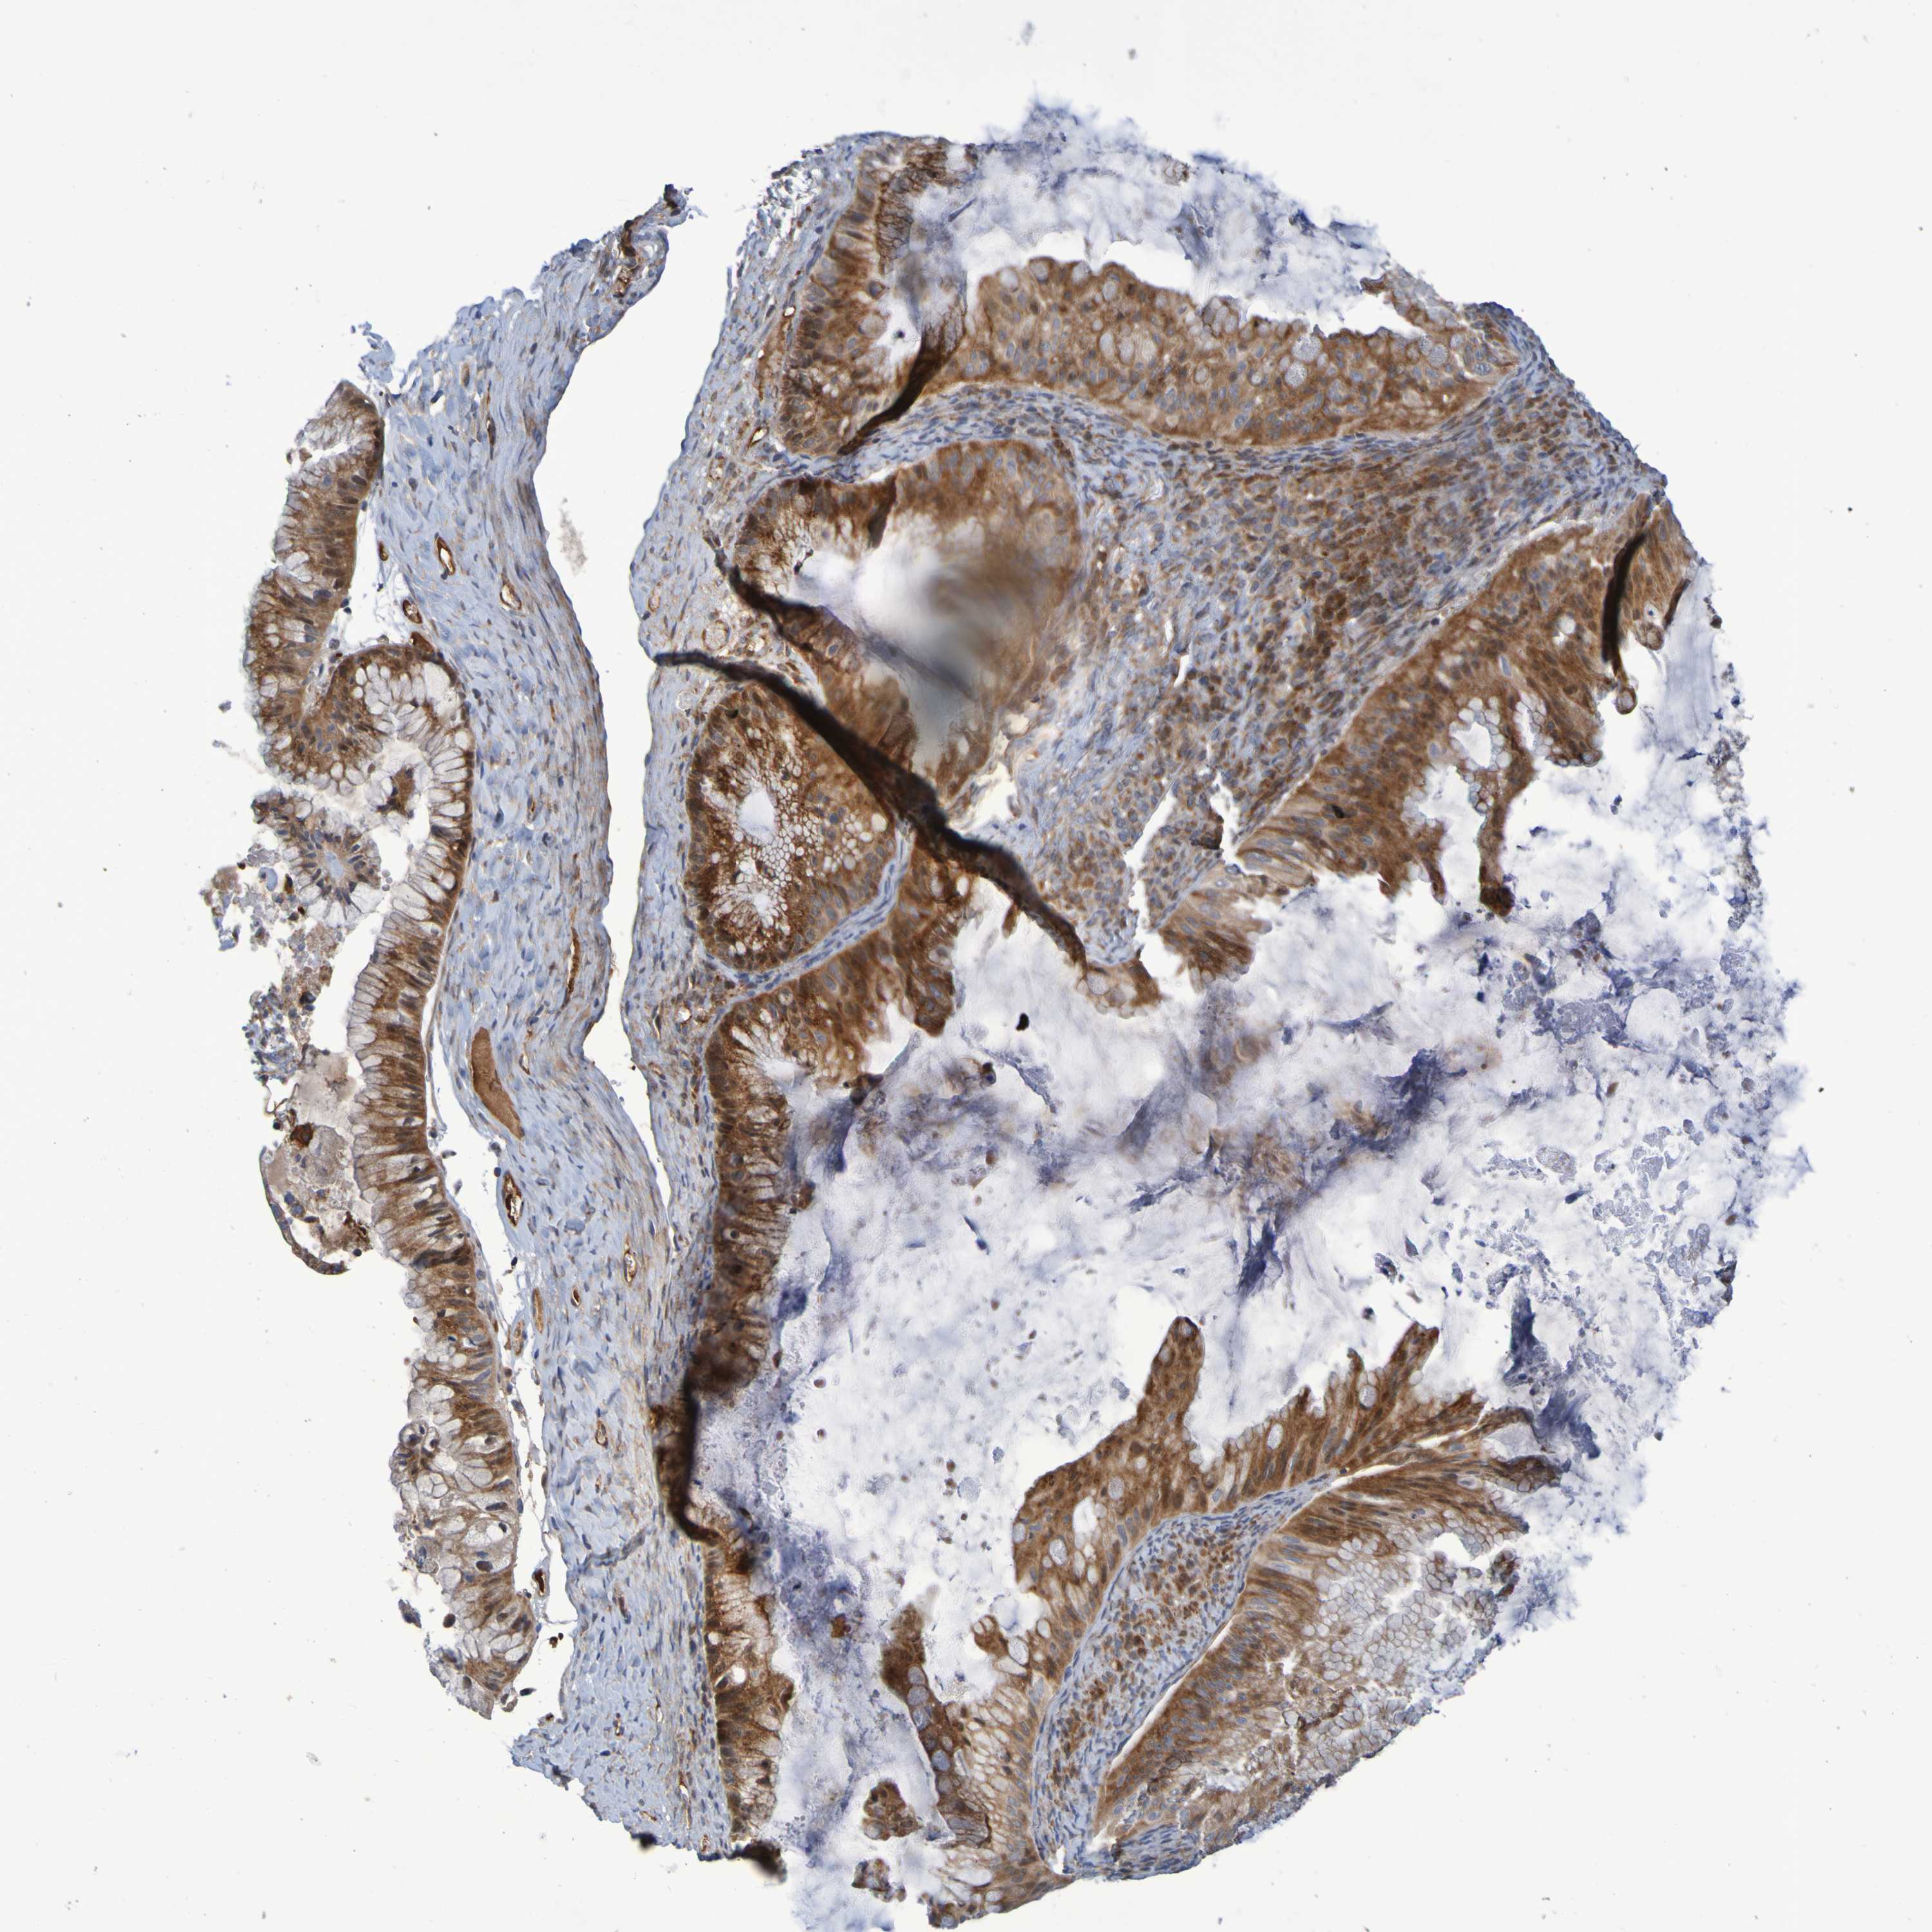

OVARIAN CANCER - Protein expressioni

A mouse-over function shows sample information and annotation data. Click on an image to view it in a full screen mode. Samples can be filtered based on level of antibody staining by selecting one or several of the following categories: high, medium, low and not detected. The assay and annotation is described here.

Note that samples used for immunohistochemistry by the Human Protein Atlas do not correspond to samples in the TCGA dataset.

Antibody stainingi

Antibody staining in the annotated cell types in the current human tissue is reported as not detected, low, medium, or high, based on conventional immunohistochemistry profiling in selected tissues. This score is based on the combination of the staining intensity and fraction of stained cells.

Each image is clickable and will lead to virtual microscopy that enables deeper exploration of all samples and also displays staining intensity scores, fraction scores and subcellular localization as well as patient and tissue information for each sample.

Antibody HPA010980

Antibody HPA011408

Staining

High

Medium

Low

Not detected

Intensity

Strong

Moderate

Weak

Negative

Quantity

>75%

75%-25%

<25%

None

Location

Nuclear

Cytoplasmic/membranous

Cytoplasmic/membranous,nuclear

Cystadenocarcinoma, serous, NOS

Carcinoma, endometroid

Cystadenocarcinoma, mucinous, NOS

Carcinoma, NOS